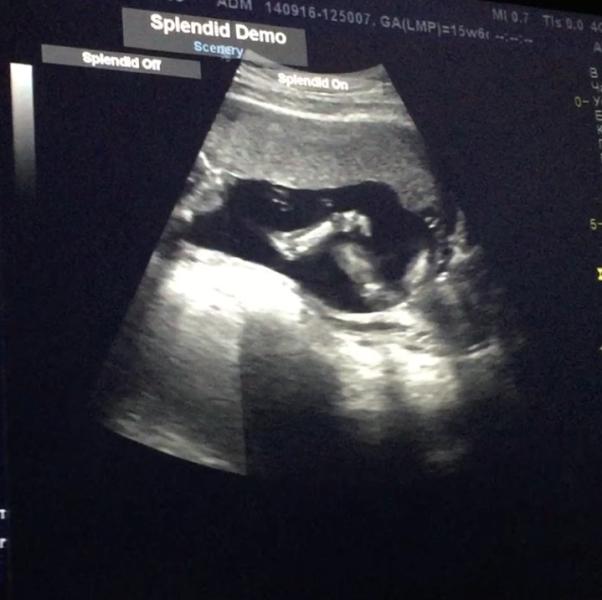

Сходили мы узнать пол )но я жутко расстроена специалистом 😞мало того ,что мы ей деньги платим ,так она начала ,а зачем вам пол ,вы молодые и первый ребёнок 😕😕😕😕

Значит я легла на кушетку ,смотрит на меня и говорит :"ой тут даже ещё тела нет ,сколько тебе лет"😕всмысле ????

Начала смотреть (по животу )все как то бегло и не то что нужно 😕

Вообщем ,хорошо ,что муж снимал на видео и я смогла вырезать нужные моменты , она даже не написала КТР ,что я очень хотела узнать 😕

Пол предположи...